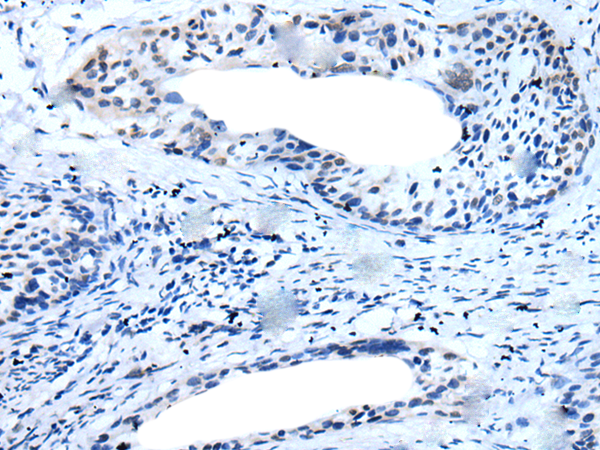

IHC positive control: |

Human cervical cancer |

IHC Recommend dilution: |

10-50 |